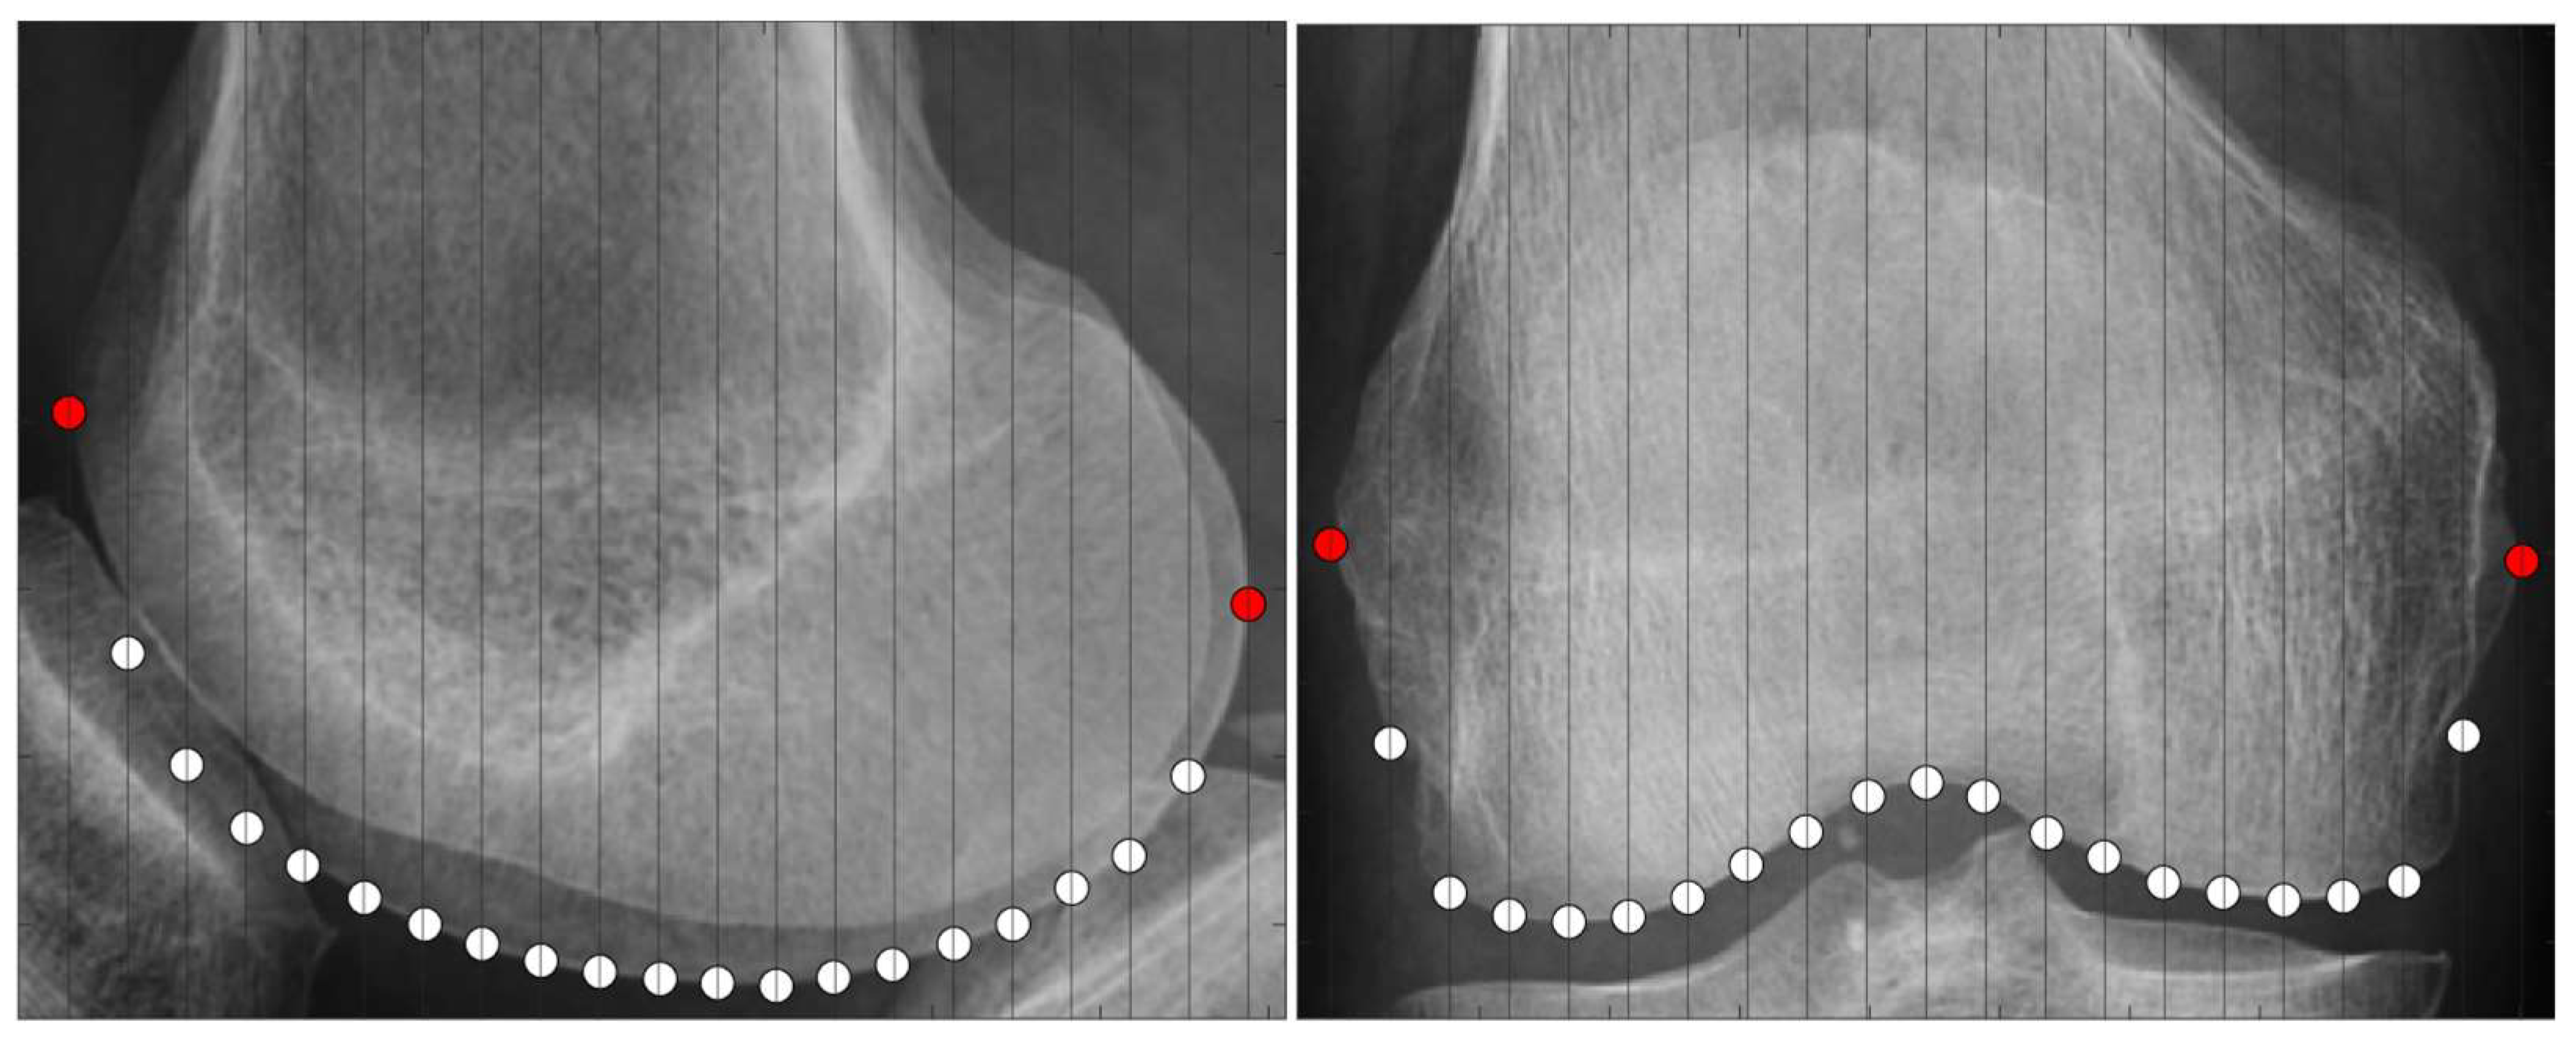

2.3.2. Scanning Feature Values

- Select two points located at both ends.

- Of the two points obtained in step 1, designate the point located posteriorly in the sagittal plane and laterally in the coronal plane as the reference point.

- Draw a perpendicular line on the images that divides the two points into n equal parts.

- Obtain the intersection of the line drawn in step 3 and the bone contour line.

- Calculate the distances between all points and the reference point and use them as the feature values.